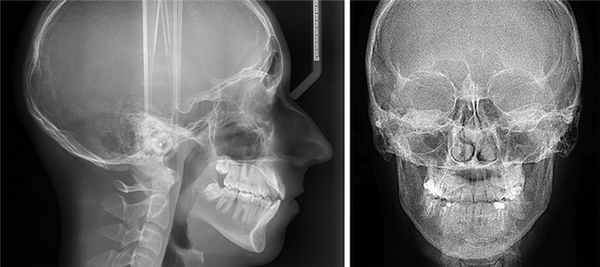

- Телерентгенограмма (ТРГ).

Телерентгенограмма (ТРГ)

Этот вид диагностики позволяет исследовать не только челюстную структуру, но и получить снимок всего черепа в фас и профиль. Относится к числу наиболее информативных диагностических процедур в стоматологии.

ТРГ проводится в обязательном порядке перед установкой брекет-систем, а также широко используется перед предстоящими операциями в качестве подготовительной меры.